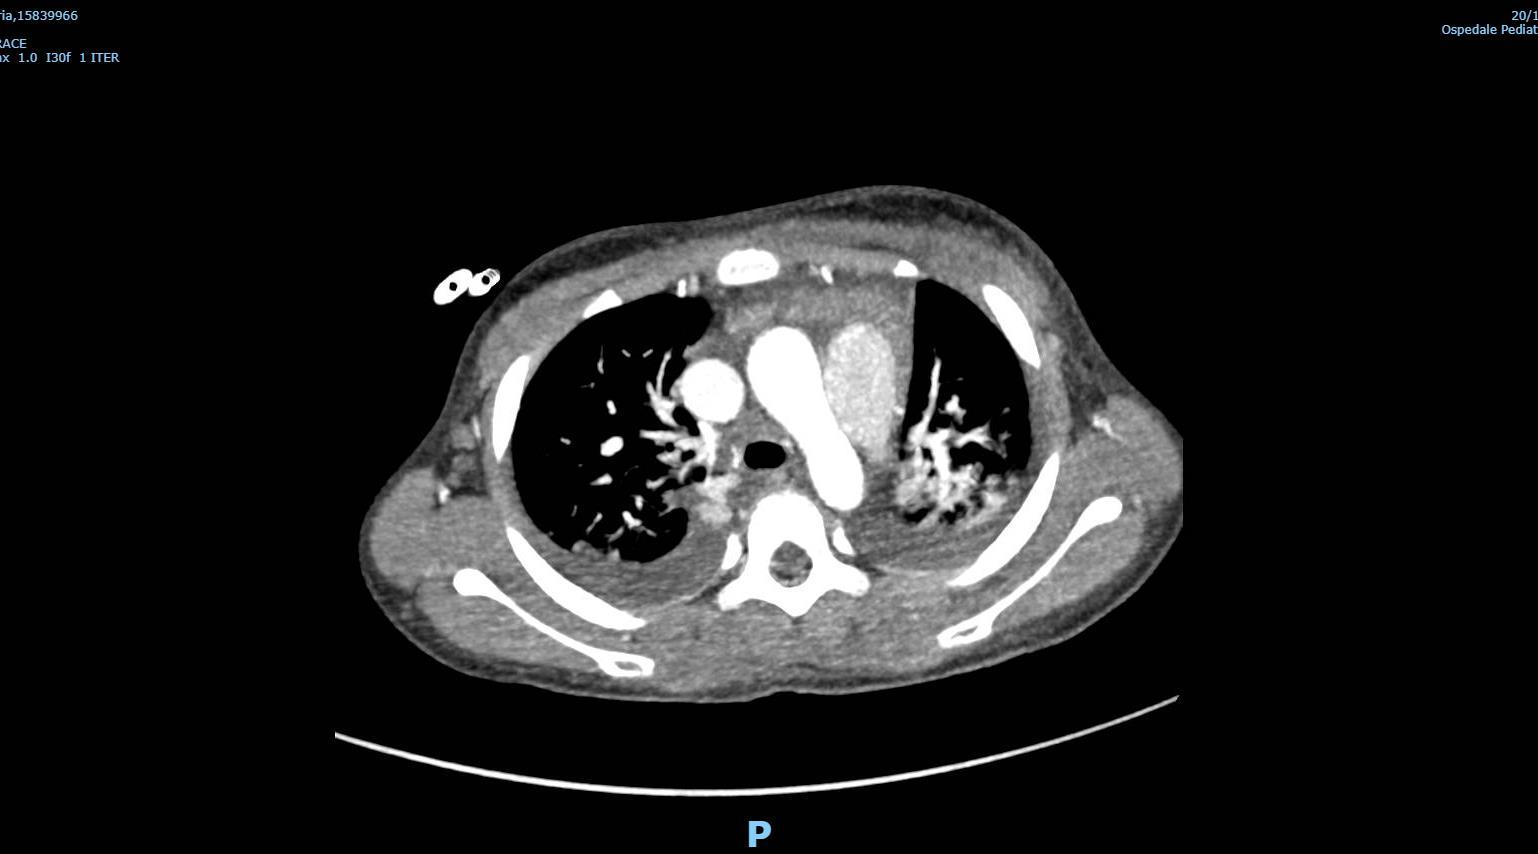

MIS-C Embolism

Imaging of Covid 19 infection in children

MIS-C: Heart failure

60 Embolus Imaging of Covid 19 infection in children

MIS-C

61